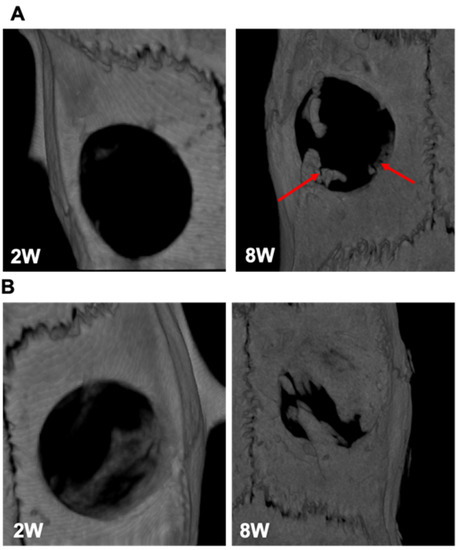

3.6. In Vivo Responses